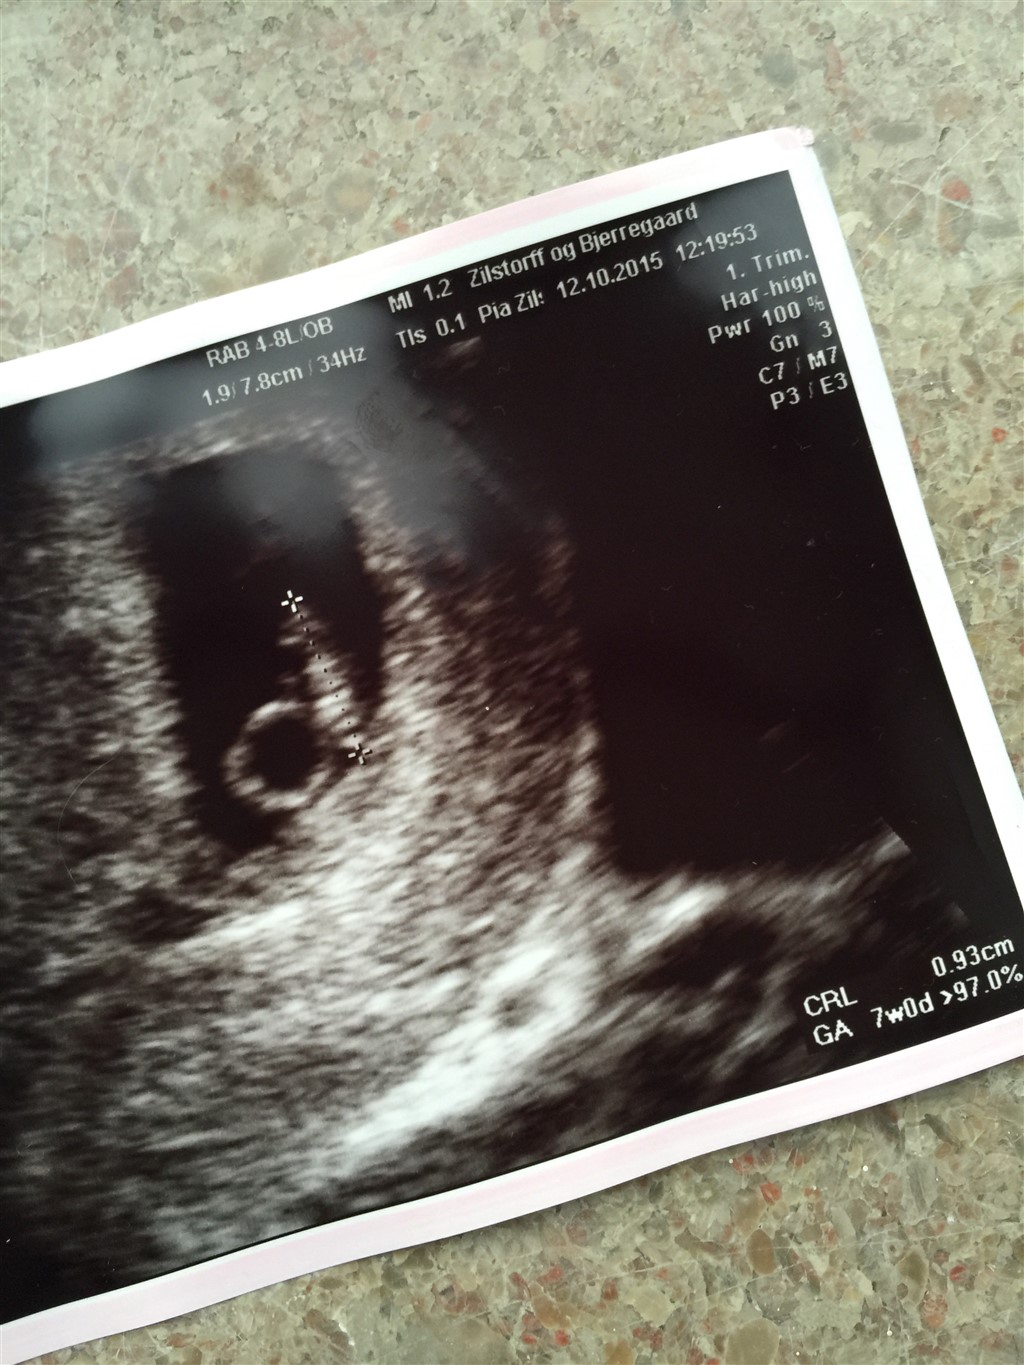

5+5 ved første skanning og Hjerteblink.

7+0 ved anden skanning og tydeligt hjerteblink

Vedhæftede fotos (klik for at se i fuld størrelse)